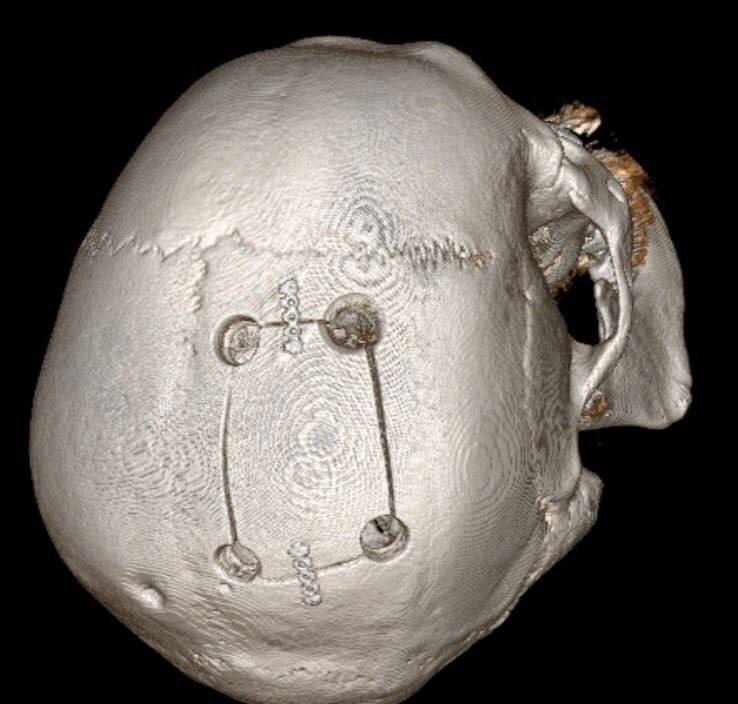

Мужчину доставили с симптомами инсульта: не двигалась левая половина тела. Но обследование показало другое — гигантское новообразование в зоне мозга, отвечающей за движение.

Нейрохирурги провели сложнейшую операцию и полностью удалили опухоль. Несмотря на высокий риск и возраст пациента, вмешательство прошло успешно.

Мозг восстановился, движения вернулись, опухоль оказалась доброкачественной. Мужчина уверенно идёт на поправку.

Фото: ГКБ Пятигорска.